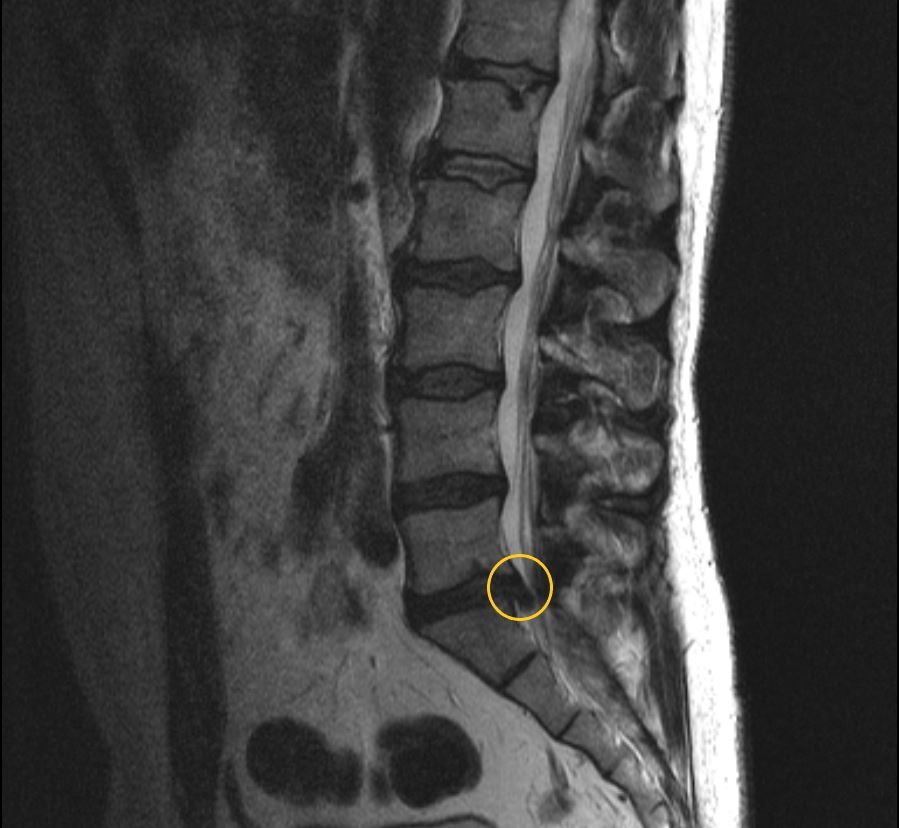

МРТ пояснично-крестцового отдела позвоночника: секвестрированная грыжа межпозвонкового диска между 5 поясничным и 1 крестцовым позвонками без сдавления нервных корешков, положение грыжи срединное.  В такой ситуации операции можно избежать. (данные собственного архива).